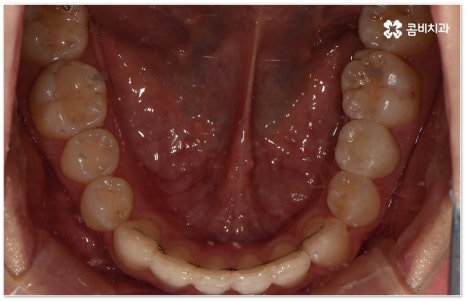

희고 가지런한 치아를 드러내며 환하게 웃는 사람을 보면 자기도 모르게 호감이 가곤하죠, 이처럼 대인 관계에서 치아는 좋은 인상을 만드는 데 심미적으로 큰 역할을 할 뿐 아니라 식사시 음식물을 저작하고 발음을 제대로 하는 데도 많은 도움을 주기 때문에 만약 타고난 치아가 삐뚤어졌거나 위아래 교합이 제대로 맞지 않는다면 이를 기능적 심미적으로 바로잡아 주기 위해서 치아 교정 치료를 고려해 볼 수 있습니다.

특히 업무적으로나 생활적으로 대인 관계가 활발하신 중장년 성인분들의 경우 치료 기간이 너무 오래 걸리지 않는지, 치아교정장치 가 너무 눈에 띄지는 않는지 궁금해 하시는 경우가 많이 있는데요. 말씀드렸던 것처럼 기술이 발달하면서 다양한 치아교정장치 가 나와있고 치아교정장치 자체는 결과에 크게 영향을 주지 않으므로 몇몇 케이스를 제외하면 환자분들께서 중요하게 생각하는 바 (심미성, 합리성 등) 를 반영할 수 있는 여지가 많이 있기 때문에 숙련된 의료진과 충분히 상담하셔서 각각의 장단점을 잘 살펴보시고 자신에게 꼭 맞는 장치를 고르시면 되니 크게 걱정하실 필요는 없을 거예요.

요즘 가장 많이 쓰이는 치아교정장치 인 클리피씨는 치아 색상의 세라믹 브라켓을 이용하기 때문에 심미성도 뛰어나고 자가결찰방식을 이용하여 보다 적은 힘으로 지속적이고 부드러운 치아 이동을 할 수 있도록 고안된 장치이므로 통증을 줄여줄 뿐 아니라 보통 2년 남짓 걸렸던 전체 교정 기간 역시 6개월 정도 감소시켜 줄 수 있습니다. 환자분들의 상황에 따라 내원 횟수 역시 줄일 수 있기 때문에 업무가 많이 바쁜 직장인분들의 경우에도 이용할 수 있다는 장점을 가지고 있어요.

이때 환자분들의 상황에 따라서 구조적인 원인이 크지 않고 교합이 심하게 어긋나지 않은 상태에서 치아의 각도만 살짝 앞으로 튀어나와 있거나 사이가 조금 벌어져 있는 등 부분 교정으로 치열을 가지런하게 바로잡을 수 있는 케이스도 있는데 이런 경우 6~8개월 정도의 보다 짧은 기간에 간편하게 치료를 끝낼 수 있으니 먼저 꼼꼼한 검진을 통해 자신이 부분 교정이 가능한지 여부를 알아보시면 좋을 거예요.

부정교합을 개선할 때 교합이 어긋난 정도가 심하고 구조적인 원인이 커서 부분 교정이 아닌 전체 교정이 필요한 케이스인 경우라고 해도 말씀드렸던 클리피씨 교정 장치 또는 보다 심미성을 강조한 치아교정장치 들의 도움을 통해 다른 사람과 얘기를 하거나 음식을 먹을 때 브라켓이 두드러지게 드러나는 부담을 줄일 수 있으니 설측교정, 콤비교정, 투명교정, 인비절라인 등에 대해서 한 번 알아보시고 각자에게 맞는 방법으로 교정 치료를 시작해 보시길 권유드리고 있어요.